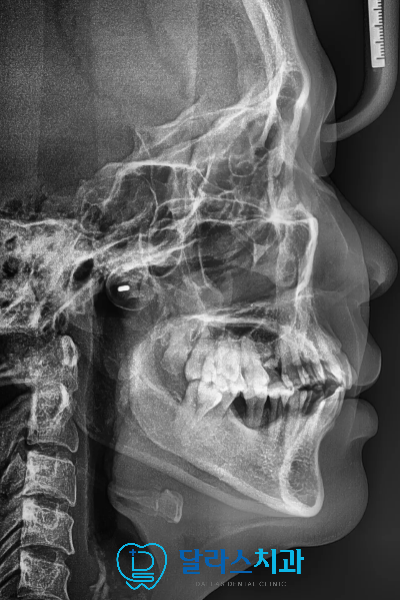

측면에서 바라보는 X-ray를 촬영하여 골격적인 부분도 함께 확인해보았습니다.

구강 내 배열을 보면 위 아래 악궁이 V자 형태로 돌출감이 있는 상태였습니다.